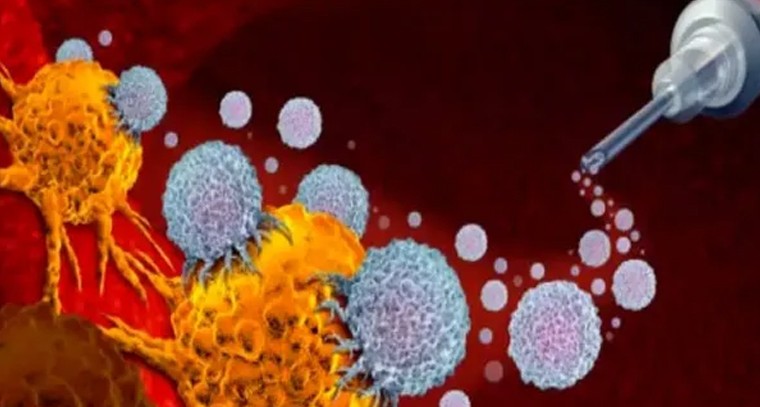

క్యాన్సర్ రాకుండా చేసే వ్యాక్సిన్ రాబోతోంది!